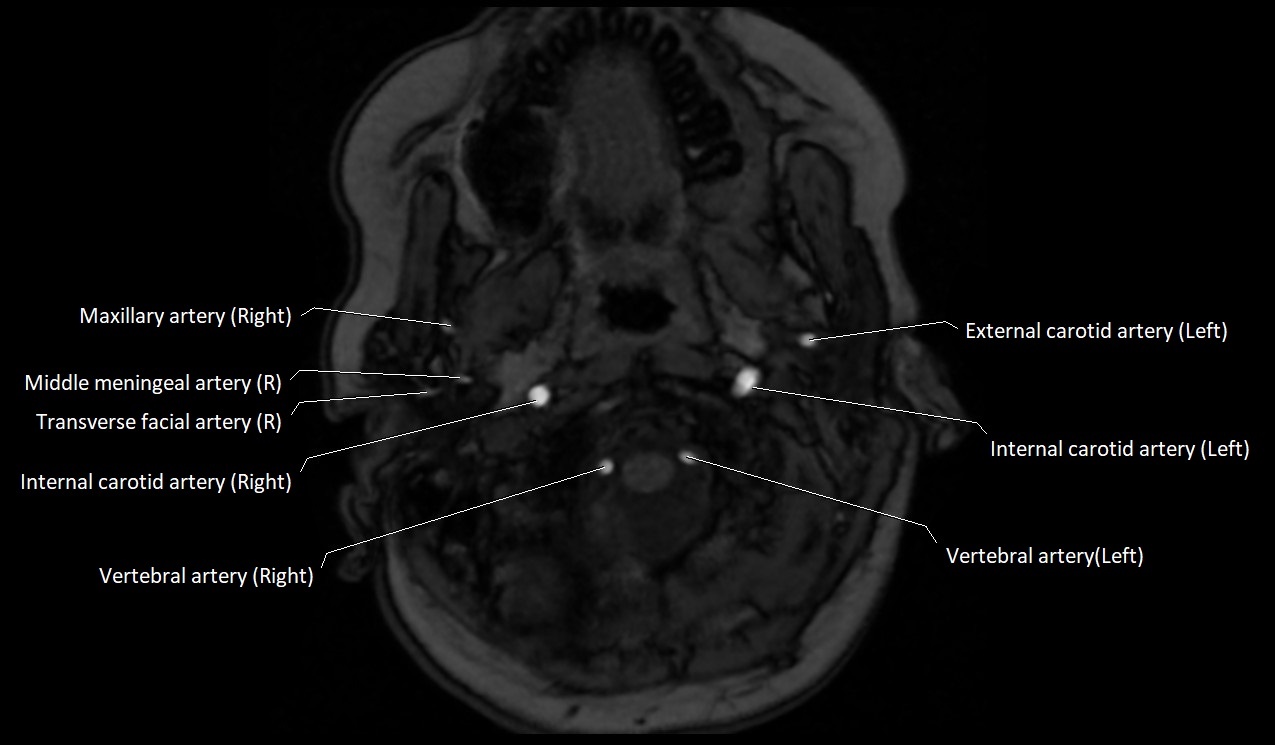

MRI images

image